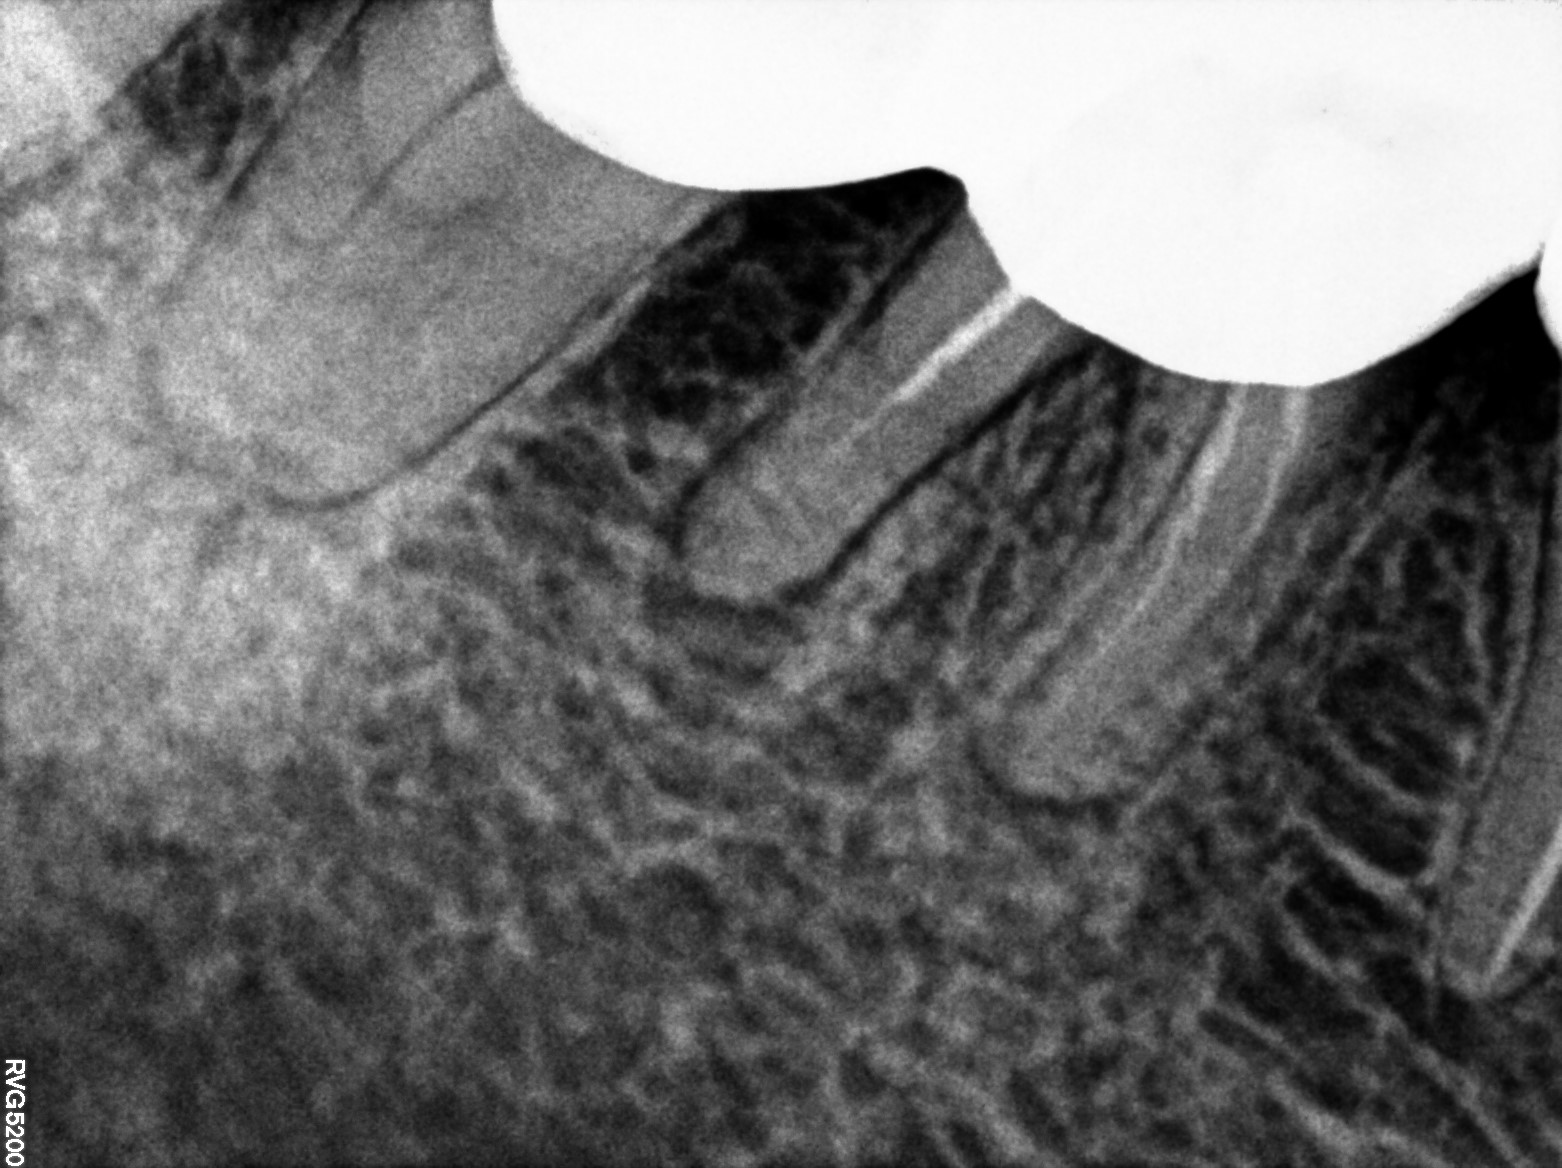

Dental Radiographs FHIR: DocumentReference · LOINC 24641-7

R59.jpg

24641-7

R54.jpg